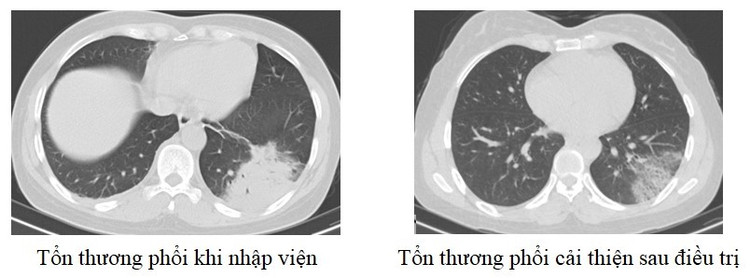

Mới đây nhất là trường hợp người bệnh nữ 48 tuổi, địa chỉ ở Lập Thạch, Vĩnh Phúc vào viện vì ho khạc đờm, sốt cao. Xét nghiệm máu cho thấy chỉ số viêm tăng cao, chụp phổi ghi nhận đông đặc diện rộng phổi trái. Người bệnh được điều trị tích cực và ra viện sau 1 tuần điều trị.

| Tổn thương phổi trên phim chụp của bệnh nhân 48 tuổi - Ảnh BVCC |